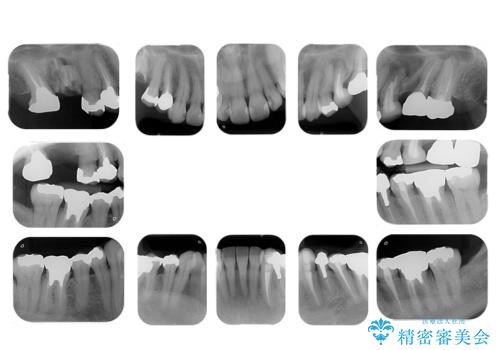

- 右上の奥歯が虫歯でかけてしまっているとのことで来院。

かかりつけ医がいたが、初めは根の治療をラバーダム治療をしてもらえたが、病院を同じドクターが移ってからはラバーダムは使用しない治療になってしまったとのことです。

全体的な治療をご希望でした。

左上56および右上6は保存が難しい状態だったためやむなく抜歯し、根の治療が必要な歯は治療をやりなおしました。

左上の欠損に関しては根の先の炎症も大きく骨も薄い状態だったため、インプラントにしていくには骨を増やす手術が必要になると説明したところ、手術を回避し義歯を希望されました。ノンクラスプデンチャーを作成しています。

根管治療は六本木院の林院長を希望されたため、治療をやり直した箇所はすべてそちらで行っています。